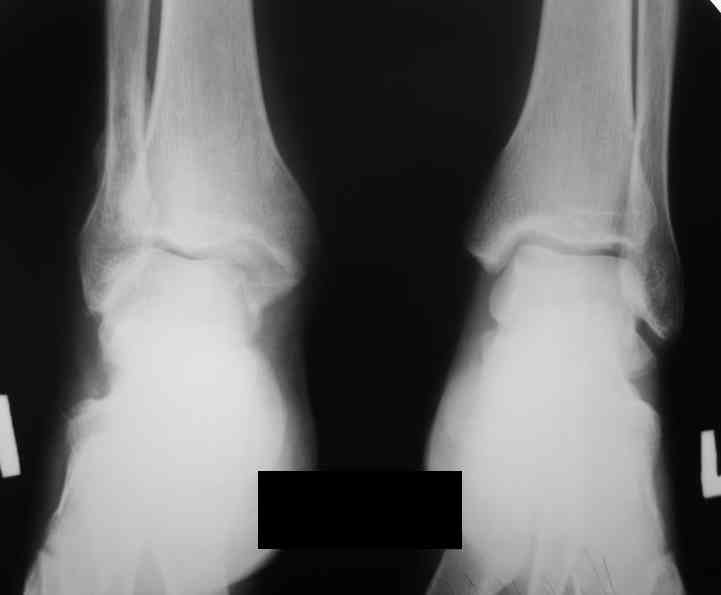

Уважаемые коллеги. Хотелось бы услышать ваше мнение по следующему случаю Обратился больной 23 года, травма 4 месяца назад - закрытый перелом наружной, внутренней лодыжки правой голени. Лечился консервативно, гипсовой иммобилизацией 8 недель, после снятия последней прошел курс восстановительного лечения. Беспокоят боли в области правого голеностопного сустава больше в проекции внутренней лодыжки, к вечеру. Отечность области сустава при физических нагрузках.Походка не изменена. Контуры правого голеностопного сустава сглажены. Имеется вальгусная установка правой пяточной кости. Объем движений в голеностопном суставе подошвенное / тыльное сгибание 50/0/80, безболезненные. Посоветуйте что делать в данной ситуации. Мне видится следующий вариант решения данной деформации: Восстановление нормальной анатомии голеностопного сустава - остеотомия малоберцовой кости и внутренней лодыжки, удалить все рубцы из области дистального межберцового синдесмоза, восстановить длину и устранить ротационное смещения наружной лодыжки.( встанет ли таранная кость на место?), фиксация наружной лодыжки пластиной, внутренней - винтами, дистального межберцового синдесмоза винтом. ЭОПом не располагаем. Что вы посоветуете? Где могут быть - технические трудности, <подводные камни>.

Здесь поаккуратней. Перелом тип В, возможно имеется только частичный разрыв дистальной порции передней тибио-фибулярной связки...и все. "Удалить все рубцы из области дистального межберцового синдесмоза", значит приговорить его к синостозу.

1) непросто определить линию перелома наружной лодыжкию но рубить надо по ней именно потому, что это перелом тип В, связки синдесмоза пострадали минимально. Если сделать остеотомию выше, то для устранения укорочения м\б кости синдесмоз придется разрушать - это не есть хорошо.

Доступ к наружной лодыжке лучше сделать передне внутренний что бы хорошо видеть неповрежденный внутренний угол суставной вилки - это будет референс для правильной позиции таранной кости.

Доступ к малоберцовой кости тоже нужен передне - наружный для того что бы была возможность выполнить остеотомию м.берцовой и остеотомию наружной части б.берцовой. Нет сомнений, что этот угол перенес компрессию. Если не опустить эту часть суставной поверхности , то невозможно будет компенсировать валгус. Для удержания фрагмента я бы использовал 3 кортикальный трансплантат из